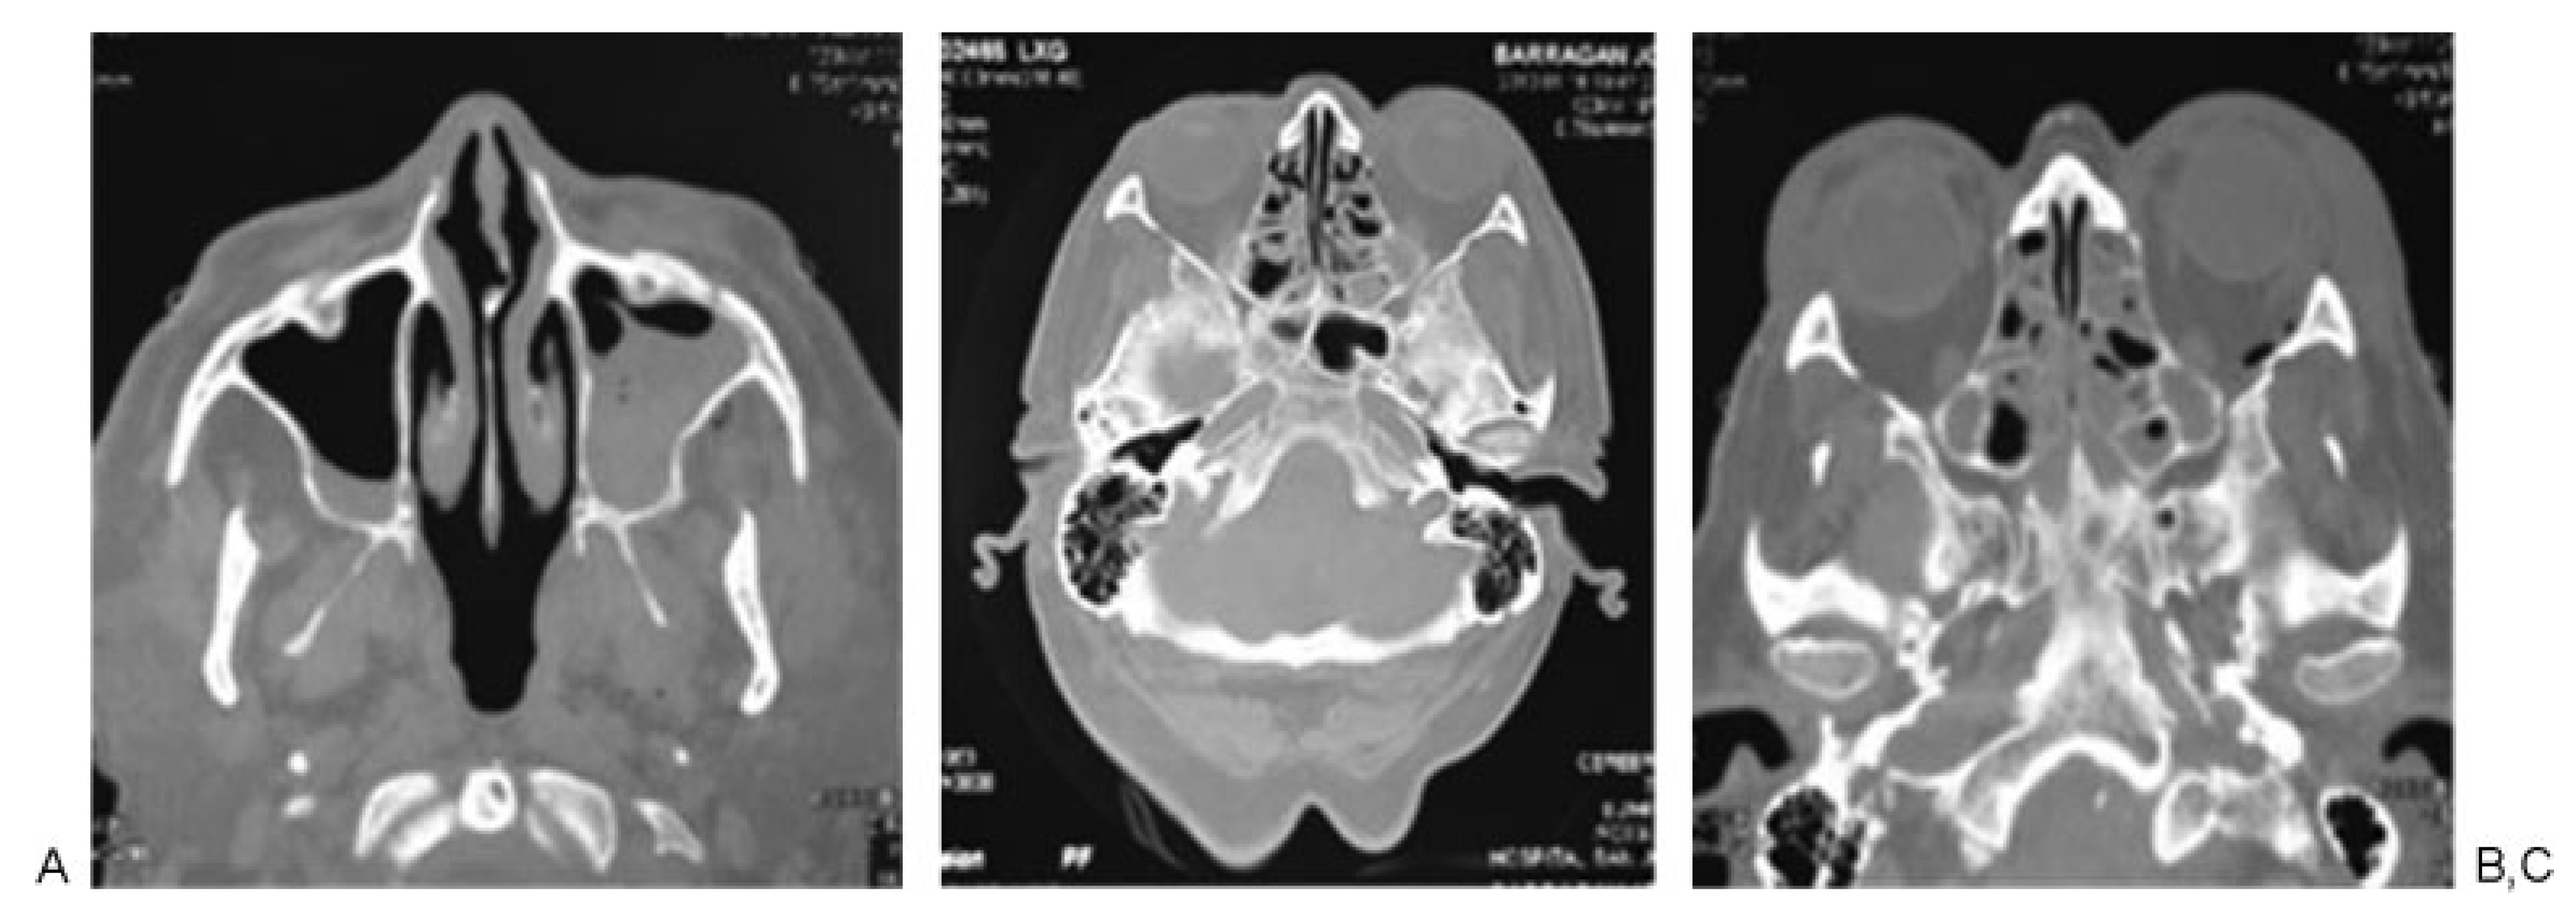

According to Manson’s classification, 17.9% (n ¼ 38) of the trauma in the group corresponded to high-energy trauma, followed by medium-energy trauma at 33.5% (n ¼ 71) and low-energy trauma at 48.6% (n ¼ 103). Among the patients with high-energy trauma, 31.5% (n ¼ 12) had combined fractures of the sphenoid bone and sphenoid sinus and 31.5% (n ¼ 12) had sphenoid sinus fractures only. In contrast, 1.4% (n ¼ 3) of patients with middle-energy trauma had sphenoid bone fractures, 5.6% (n ¼ 4) of the patients had sphenoid sinus fractures, and 4.2% (n ¼ 3) of the patients had sphenoid bone and sphenoid sinus fractures. In the low-energy trauma group, only 1 patient presented sphenoid sinus fracture (0.97%; Table 3; Figure 2, Figure 3 and Figure 4).

Figure 2. Patient 1: high-energy trauma and panfacial fractures. (A) Zygomatic arch, malar, and upper jaw fractures. (B) Sphenoid sinus fracture. (C) Computed tomography three-dimensional reconstruction showing the fractures at the middle third and jaw.